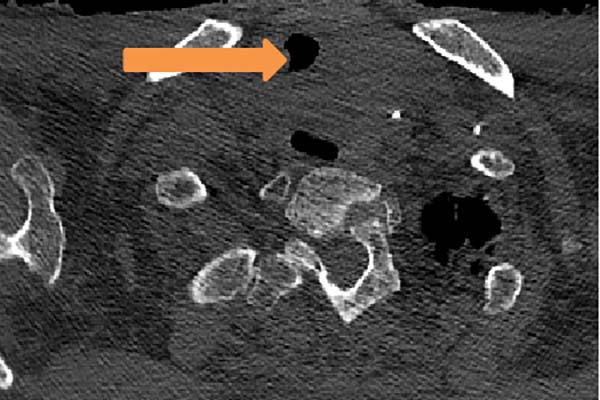

术前CT(箭头处为气道最狭窄处)

图1术后CT(箭头处为原气道最狭窄处)